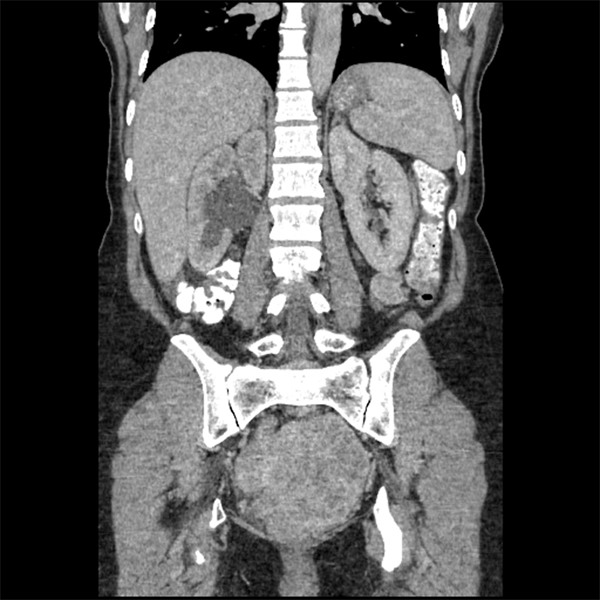

A 50-year-old premenopausal woman presents with a several-month history of indigestion. She has also recently noticed a palpable left lower quadrant mass. Her cancer antigen 125 levels are found to be elevated…. https://bit.ly/35sunFU

#ACRCaseinPoint pic.twitter.com/eZSl7rTw7H